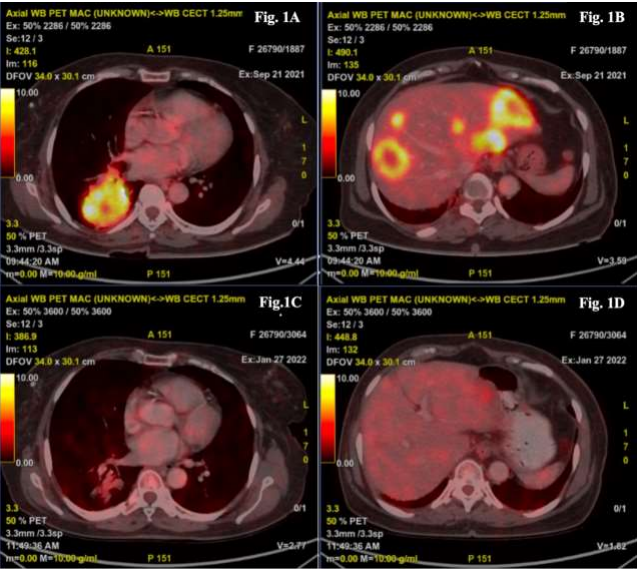

A 67-year-old non-smoking female presented in October 2021 with a 3-month history of cough with expectoration, loss of appetite, and significant weight loss. Her Eastern Cooperative Oncology Group Performance Status (ECOG PS) was 2. She had done a CT scan at a different centre in September 2021 which showed an 87x71x49mm right lung lower lobe lesion, mediastinal lymphadenopathy, and liver lesions. Biopsy done from the lung lesion revealed Adenocarcinoma which was confirmed to be of pulmonary origin through immunohistochemistry which showed TTF1 and Napsin A positivity. Staging PET-CT (Fig 1A & 1B) revealed metabolically active right lower lobe lung lesion, hypermetabolic metastatic mediastinal & retroperitoneal lymphadenopathy (largest coeliac lymph node), active peritoneal soft tissue deposit in right paracolic region and multiple bilobar hepatic metastatic lesions. Contrast MRI brain showed no evidence of disease. Molecular Lung Panel by Next Generation Sequencing detected 2 missense mutations in EGFR exon 18 – Gly719Ala (G719A) and Glu709Ala (E709A). She was started on Afatinib 30 mg/d on 27th October 2021. After 1 month of therapy, she developed grade 2 diarrhoea as per CTCAE and was managed conservatively. By this time, her cough had resolved. Dose increment to 40 mg was discussed with the patient but she opted to continue the same dosage. After completing 3 months of therapy, her ECOG PS had improved to 0. She had grade 1 diarrhoea and grade 2 dysgeusia as per CTCAE. Response evaluation PET CT (Fig 1C & 1D) scan on 27th January 2022 showed significant metabolic response and volume reduction in lung lesion, mediastinal and retroperitoneal lymphadenopathy, peritoneal deposit and also in bilobar hepatic lesions (Table 1). She took Afatinib therapy at 30mg/d till April 2022 before being lost to follow-up.

IMAGE 1

1A) Right Lung lower lobe mass (pre-treatment)

1B) Metastatic Liver lesions (pre-treatment)

1C) Right Lung lower lobe mass showing significant metabolic response after 3 months of Afatinib

1D) Liver lesions showing significant metabolic response after 3 months of Afatinib